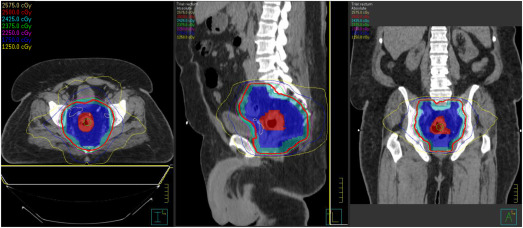

A mid-treatment break and reassessment maintains tumor control and reduces toxicity in patients with hepatocellular carcinoma treated with stereotactic body radiation therapy.

Radiother Oncol. 141: 101-107Jackson W.C. Tang M. Maurino C. et al.

Individualized Adaptive Radiation Therapy Allows for Safe Treatment of Hepatocellular Carcinoma in Patients With Child-Turcotte-Pugh B Liver Disease.

Int J Radiat Oncol Biol Phys. 109: 212-219Baumann B.C. Wei J. Plastaras J.P. et al.

Stereotactic Body Radiation Therapy (SBRT) for Hepatocellular Carcinoma: High Rates of Local Control With Low Toxicity.

Am J Clin Oncol. 41: 1118-1124Jackson W.C. Hartman H.E. Gharzai L.A. et al.

The Potential for Midtreatment Albumin-Bilirubin (ALBI) Score to Individualize Liver Stereotactic Body Radiation Therapy.